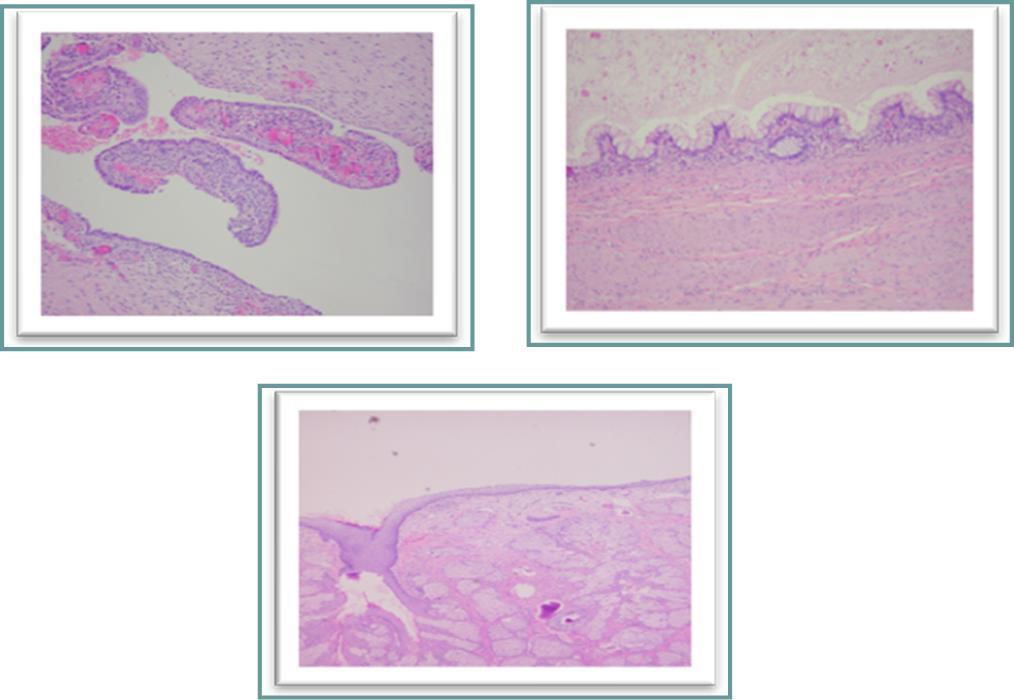

Figure 4(a, b, c).Histological examination. a, cyst lined by endometrial epithelium overcoming its endometrial stroma corresponding to an endometriosis cyst. b, a portion of the cystic mature teratoma lined with intestinal-type mucosa. c, skin surface-like structure with many sebaceous glands found on another part of the cyst.

Histological examination.  a, cyst lined by endometrial epithelium overcoming its endometrial stroma corresponding to an endometriosis cyst.  b, a portion of the cystic mature teratoma lined with intestinal-type mucosa.  c, skin surface-like structure with many sebaceous glands found on another part of the cyst.